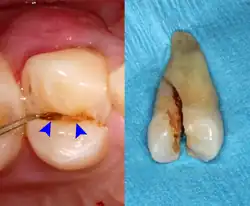

Dental trauma and cracked tooth syndrome

Cracked tooth syndrome refers to a highly variable[30] set of pain-sensitivity symptoms that may accompany a tooth fracture, usually sporadic, sharp pain that occurs during biting or with release of biting pressure,[31] or relieved by releasing pressure on the tooth.[10]: 24 The term is falling into disfavor and has given way to the more generalized description of fractures and cracks of the tooth, which allows for the wide variations in signs, symptoms, and prognosis for traumatized teeth. A fracture of a tooth can involve the enamel, dentin, and/or pulp, and can be orientated horizontally or vertically.[10]: 24–25 Fractured or cracked teeth can cause pain via several mechanisms, including dentin hypersensitivity, pulpitis (reversible or irreversible), or periodontal pain. Accordingly, there is no single test or combination of symptoms that accurately diagnose a fracture or crack, although when pain can be stimulated by causing separation of the cusps of the tooth, it's highly suggestive of the disorder.[10]: 27–31 Vertical fractures can be very difficult to identify because the crack can rarely be probed[10]: 27 or seen on radiographs, as the fracture runs in the plane of conventional films (similar to how the split between two adjacent panes of glass is invisible when facing them).[10]: 28–9

The prognosis for a cracked tooth varies with the extent of the fracture. Those cracks that are irritating the pulp but do not extend through the pulp chamber can be amenable to stabilizing dental restorations such as a crown or composite resin. Should the fracture extend though the pulp chamber and into the root, the prognosis of the tooth is hopeless.[10]: 25